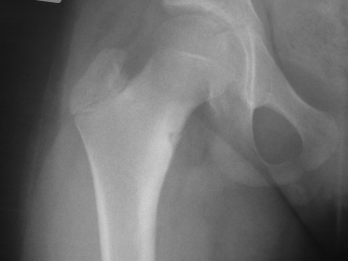

Fibröz Displazi

Fibröz displazi, normal kemik dokusunun yerini proliferatif fibröz dokunun alması ile karakterize kemiğin selim tümörüdür. Kemiğin medullar kanalından kaynaklanır. Görülme yaşı ergenlik çağı ve 20’li yaş grubudur.Monostotik ve poliostotik fibröz displazi olarak iki tipi vardır.Monostotik olanların oranı %70 dir.

Lezyon; kol ve bacak uzun kemiklerinde, kaburgada, leğen kemiğinde ve kafa-yüz kemiklerinde görülebilir. Monostotik fibröz displazi iskelet sistemi gelişmesi esnasında, poliostotik olanlar ise iskelet sistemi geliştikten sonra ortaya çıkar. Poliostotik olanların %2-3’ü endokrin rahatsızlıklarla birliktedir, ciltte sütlü kahverengi lekelerle birlikte çok kemikte lezyon var ise McCune-Albright sendromu denir. İntramusküler miksoma ile birlikte görülürse Mazabraud Sendromu denir.

Kemikte aşırı zayıflık oluşunca patolojik kırık gelişebilir. Uyluk kemiği üst ucunda lezyonun geliştiği fark edilmez ise çoban asası görüntüsü meydana gelir. Düz grafide buzlu cam görüntüsü tipiktir. Genellikle hastaların şikayeti yoktur. Şişlik ve ağrı şikayeti gelişebilir. Fibröz displazi iskelet sisteminin gelişimi ile birlikte büyür. İskelet büyümesi tamamlanınca lezyonun gelişimi yavaşlar.